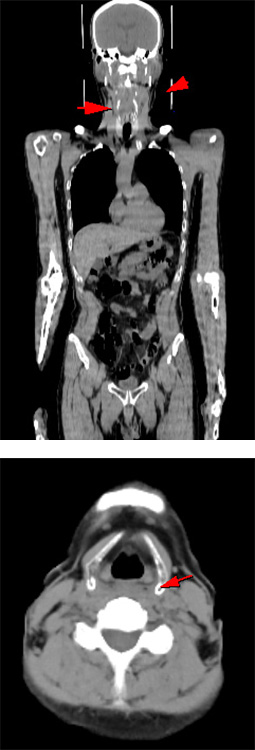

治療後経過観察にて以前の病変近傍に新たな病変出現(再発)

悪性リンパ腫